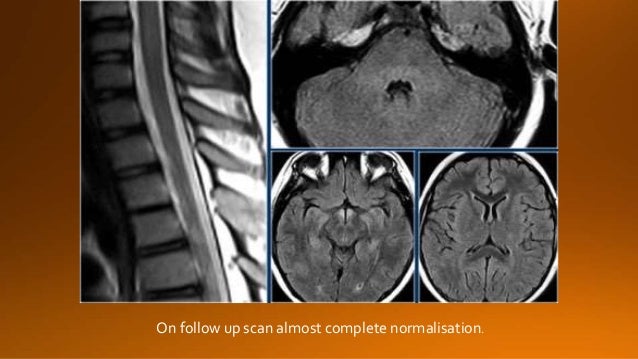

Your message goes here

26. 26. On follow up scan almost complete normalisation.